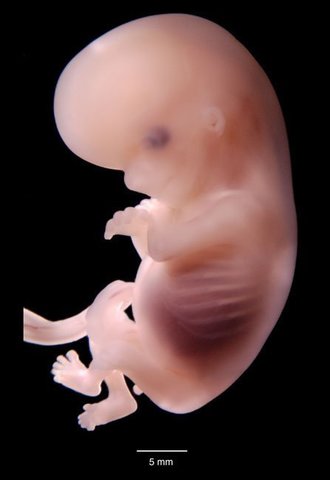

Segundo mes

El bebé ha crecido de forma espectacular dentro del útero materno en la semana 8 de embarazo. A partir de esta semana, deja de ser considerado un embrión para considerarse un feto.